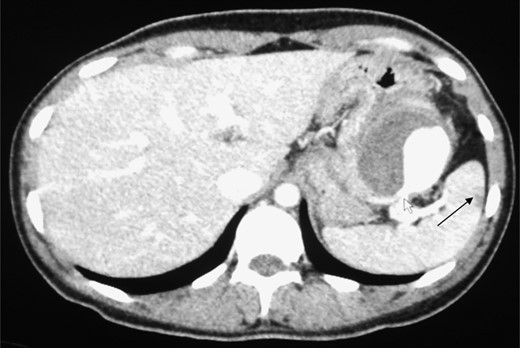

A triphasic, contrast enhanced computed tomography (CT) scan revealed a 6 cm × 5.2 cm well defined, heterogeneous, hypodense mass arising from the pancreatic tail, with an extremely enhancing component (200 Hounsfield units) on its lateral side, a feeder vessel arising from the splenic artery and a small splenic infarct (Fig. 1). Fascial margins of the mass were poorly defined from the splenic hilum and splenic flexure of the large intestine (Fig. 2). CT imaging was supportive of a differential diagnosis of a solid pseudopapillary tumor of the tail of the pancreas with invasion of the colonic wall and compression of the stomach.

CT shows the point of communication (free rupture) between the aneurysm and splenic flexure of the colon.